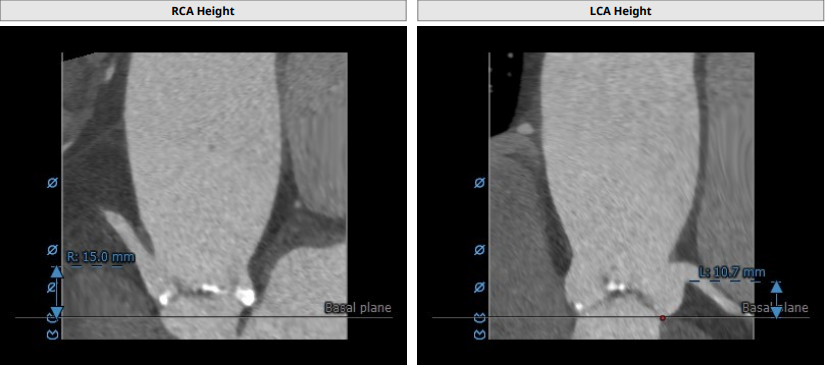

CT报告评估:

Annulus:24.4mm,LVOT:22.6mm,Asc.Ao:43.4mm,STJ:30.7mm。

LCA:10.7mm,RCA:15.0mm。

瓣环结构及钙化情况:患者为TYPE 1型二叶瓣,瓣环及左室流出道呈上宽下窄型结构,钙化积分为529,主要集中于无冠窦,从基底部开始延申至左右融合处及无冠窦游离缘,整体窦部空间合适。

心室情况:升主动脉增宽,心脏角度59°,严重心肌增厚,心室腔小。